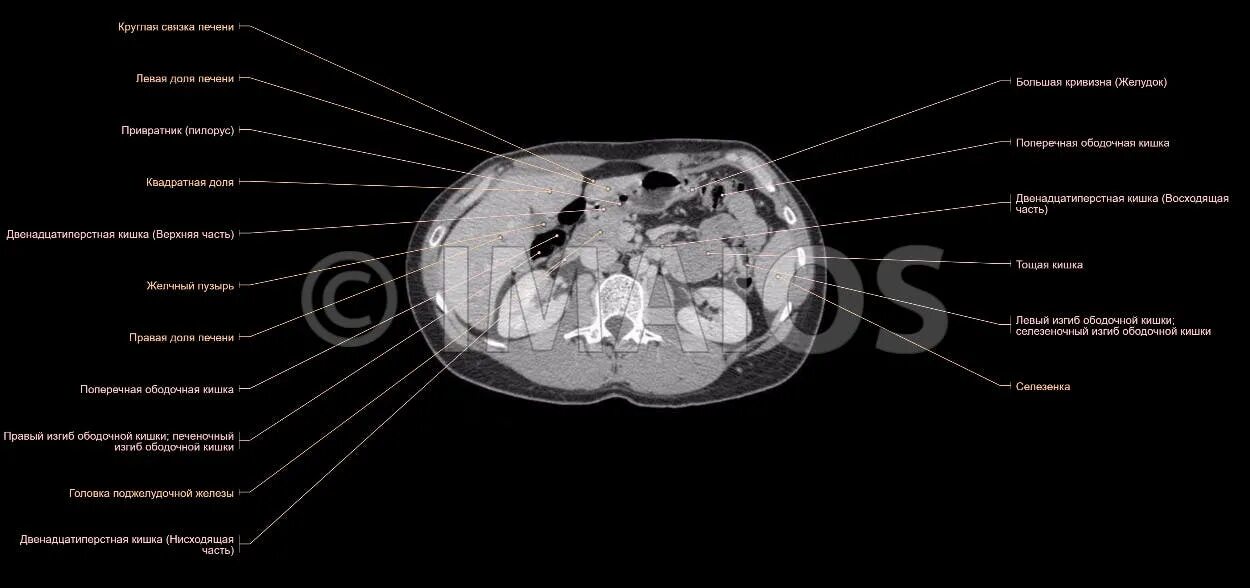

Атлас кт мрт